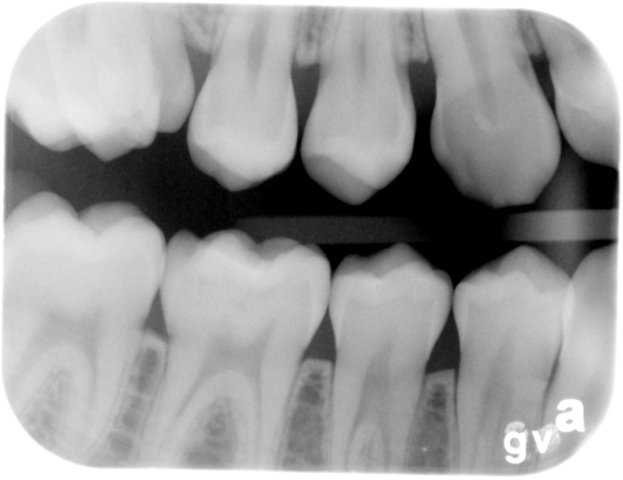

• TÉCNICA DE BISECTRIZ DEL ÁNGULO O CONO CORTO

TÉCNICA DE BISECTRIZ DEL ÁNGULO O CONO CORTO

LIBRO DE CONSULTATÉCNICA DE BISECTRIZ DEL ÁNGULO, PRINCIPIOS1913.- Weston Price.- Ley de isometría de la Técnica Radiográfica Periapical de Bisectriz ó de Cono Corto.

• TÉCNICA DE PARALELISMO

TÉCNICA DE PARALELISMO

TÉCNICA DE PARALELISMO1947.- Gordon Fitzgerald.- Padre de la Radiología moderna. Técnica de paralelismo de cono largo.